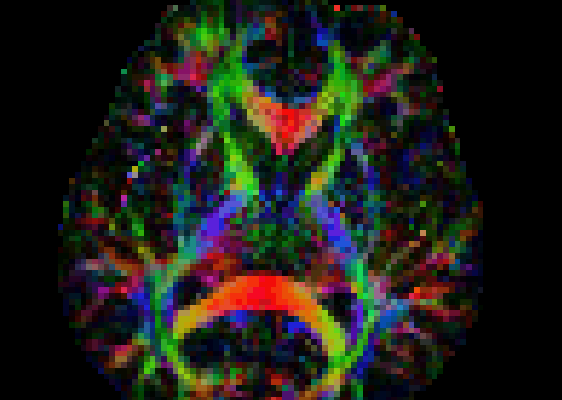

MRI image analysis

Liz: Today's guest post comes from Matt Hall at UCL. Call me easily